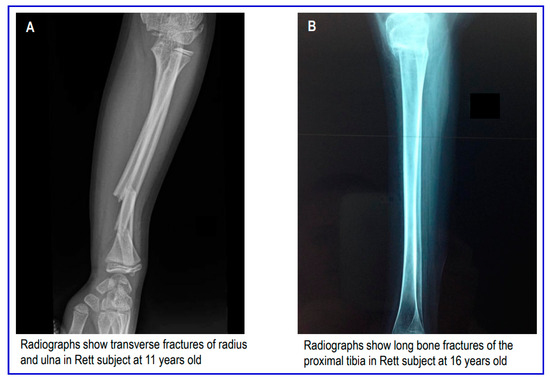

Bone Fracture in Rett Syndrome: Mechanisms and Prevention Strategies

by Carla Caffarelli, Antonella Al Refaie, Caterina Mondillo, Michela De Vita, Leonardo Baldassini, Giuseppe Valacchi and Stefano Gonnelli

The present study aimed to evaluate the burden and management of fragility fractures in subjects with Rett syndrome. We searched all relevant medical literature from 1 January 1986 to 30 June 2023 for studies under the search term “Rett syndrome and fracture”. The fracture frequency ranges from a minimum of 13.9% to a maximum of 36.1%. The majority of such fractures occur in lower limb bones and are associated with low bone mineral density. Anticonvulsant use, joint contractures, immobilization, low physical activity, poor nutrition, the genotype, and lower calcium and vitamin D intakes all significantly impair skeletal maturation and bone mass accrual in Rett syndrome patients, making them more susceptible to fragility fractures. This review summarizes the knowledge on risk factors for fragility fracture in patients with Rett syndrome and suggests a possible diagnostic and therapeutic care pathway for improving low bone mineral density and reducing the risk of fragility fractures. The optimization of physical activity, along with adequate nutrition and the intake of calcium and vitamin D supplements, should be recommended. In addition, subjects with Rett syndrome and a history of fracture should consider using bisphosphonates. Full article